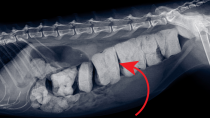

Constipation and Megacolon Casestudy: Can Surgery Save A Cat from Misery?

Is your cat constipated? Don't wait to take action!